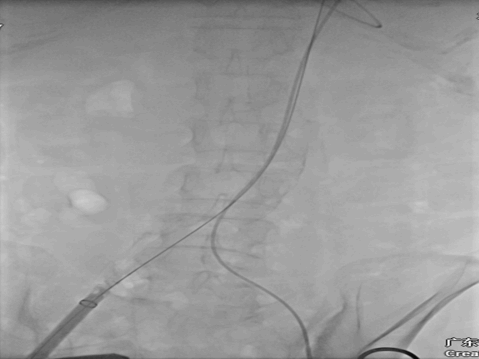

术中DSA:

8*60外周球囊扩张DSA